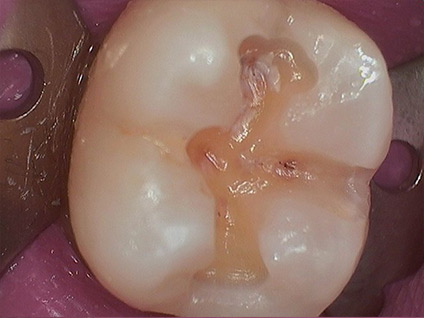

2. Revealing Decay

3. Decay Removed